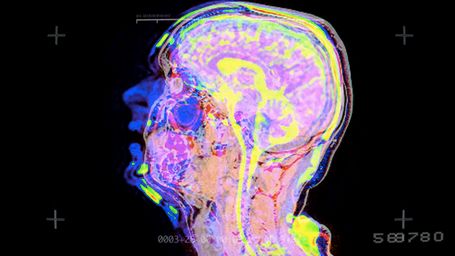

Pomysł na ubranie twórczości Sivu w formę naukową i technologiczną wziął się z badań nad wrodzonym rozszczepem wargi i podniebienia. Badania te prowadzone są przez St Bartholomew's Hospital i sponsorowane przez kilka organizacji charytatywnych w Londynie. Sivu postanowił promować inicjatywę poprzez nakręcenie wideoklipu wykorzystującego skaner MRI, który jest głównym narzędziem do diagnozowania zmian w twarzoczaszce.

W projekt zaangażowali się lekarze prowadzący badania, Marc E. Miquel oraz Andrew D Scott i udostępnili skaner dla potrzeb artysty. Reżyserią klipu zajął się Adam Powell, a za efekty specjalne (HUD/interfejs) odpowiada Lewis Kyle White.